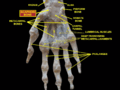

Scaphoid bone. Scaphoid shown in yellow. Left hand. Palmar surface.

Scaphoid shown in yellow. Left hand. Palmar surface. Scaphoid shown in yellow. Left hand. Dorsal surface.